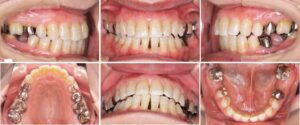

叢生(デコボコ)、口元突出、口唇閉鎖不全を主訴とした大人の矯正治療についてご紹介いたします。

24才女性の症例です。

「前歯のデコボコが気になる、結婚式までに綺麗にしたい」と相談に来られました。

詳しく調べてみると、顎の位置も不安定であった為、まず「顎の位置を安定させる装置(スプリント)」を使って、顎位の安定を図りました。

その後、矯正治療を行いました。

上下の左右4番の歯を抜歯し、マルチブラケット装置(ワイヤーの装置)や上顎に力をかける器具(パラタルバー)、アンカースクリューを使って歯列と咬合の改善を図りました。

矯正治療費用:¥1,034,000

矯正治療期間:2年7ヶ月

矯正治療回数:19回

治療前

治療中

治療後